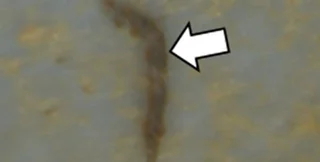

Микропластик в образце легочной ткани | Фото: Science of The Total Environment

2022 год стал переломным, так как ученые впервые обнаружили микропластик в самых глубоких отделах легких человека. Отметим, что ранее ученые также обнаружили масштабы распространения пластика на планете: крохотные фрагменты были обнаружены в телах наземных и морских животных, а также в телах людей и даже новорожденных.